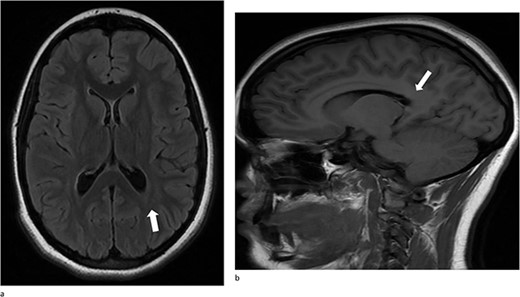

A 13-year-old female presented with an abrupt onset of a severe headache accompanied by two episodes of vomiting, left-sided jaw pain, nausea, and nasal congestion. She did not report any numbness, tingling, muscle weakness, or changes in vision. An initial non-contrast CT scan of the head revealed a left lateral intraventricular hemorrhage, (Fig. 1a). There were no intraparenchymal hemorrhages, midline shifts, or extra-axial fluid accumulations. MRI revealed a hemorrhagic lesion measuring 2.1 cm × 1.6 cm × 2.6 cm, involving the left atrium and the adjacent periventricular deep white matter (Fig. 1b). There was thickening of the choroid plexus, with no significant vasogenic edema or acute extra-axial fluid collection, and no signs of brain herniation.

(a)–(d) Demonstrates evidence of a hemorrhagic lesion involving the left atrium and adjacent periventricular deep white matter with a moderate amount of intraventricular hemorrhage within the left ventricle.

(a) and (b) Stable postsurgical findings compatible with gross total resection of left atrial and adjacent periatrial tumor. No MRI evidence of residual/recurrent mass, with normal ventricular size.